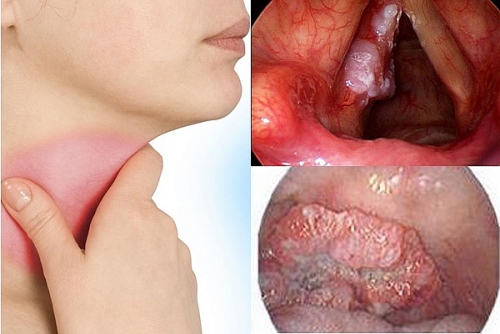

Dấu hiệu nhận biết ung thư thanh quản là gì?

Ung thư thanh quản là loại ung thư phổ biến thường gặp hiện nay. Dưới đây là những dấu hiệu nhận biết ung thư thanh quản.